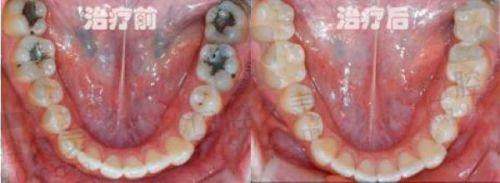

苏州赛阁中喜口腔烤瓷牙套费用不是固定不变的,会受到多个因素的影响。首先是个人口腔状况,如果您的牙齿本身存在一些问题,比如有龋齿、牙周炎等,在安装烤瓷牙套之前需要精良行治疗,这就会增加整体的费用。其次,所选材料也是影响费用的重要因素。不同材质的烤瓷牙套在性能、美观度和价格上都有差异。像钴铬合金烤瓷冠,价格相对较为亲民,大概800元起;而全瓷牙冠,如爱尔创全瓷牙冠,美观度和生物相容性更好,价格就会高一些,1600元起。